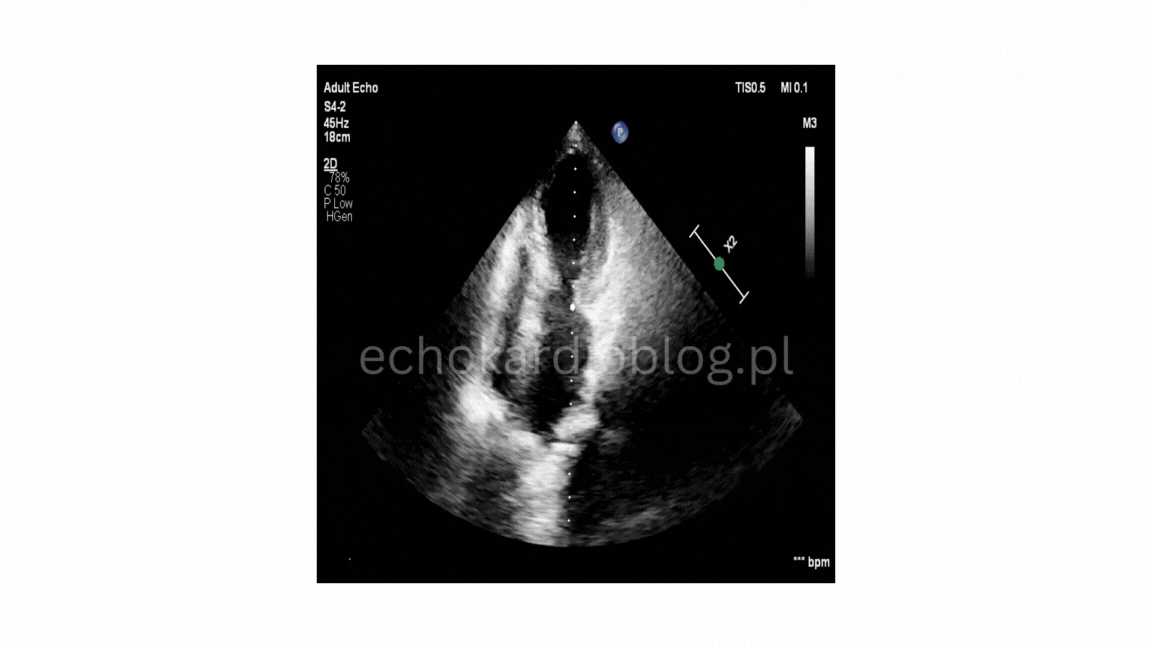

w EKG : tachykardia zatokowa, niezupełny blok prawej odnogi pęczka Hisa, fragmentacja zespołów QRS w odprowadzeniu II,III,aVF, niewielkie wklęsłe uniesienie odcinka ST w III, aVF, V5 i V6), odstęp Qtc w normie, a przede wszystkim echo serca , które wskazywało na Tako-tsubo. Rozpoznanie potwierdzono w koronarografii.

The diagnostic pitfall was the absence of a clear stressor, no chest pain, and markedly elevated D-dimers , which could initially suggest pulmonary embolism. However, further tests revised the diagnosis: elevated Troponins (966ng/l), ECG (sinus tachycardia , incomplete right bundle branch block, fragmented QRS complexes in leads II,III,aVF, slight ST-segment elevation in leads III,aVF, V5 and V6, normal Qtc interval ), and most importantly, echocardiography , which indicated Tako-tsubo cardiomyopathy . The diagnosis was confirmed by coronary angiography.